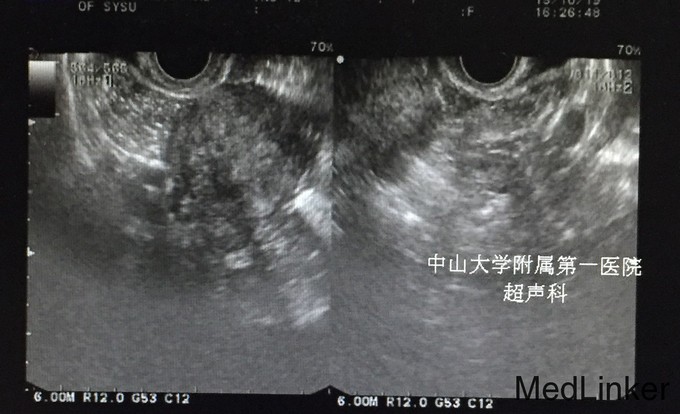

查体:;宫颈轻度糜烂,余未见异常。 辅查:.2015-10-04妇科B超:子宫增大,子宫肌瘤(后壁2.2cm*2.1cm),子宫内膜增厚,约1.8cm。 2015-10-10诊刮病理示:慢性子宫内膜炎,局部符合子宫内膜息肉,分泌期子宫内膜。 2015-10-25我院妇科B超:小型子宫肌瘤。(见图)